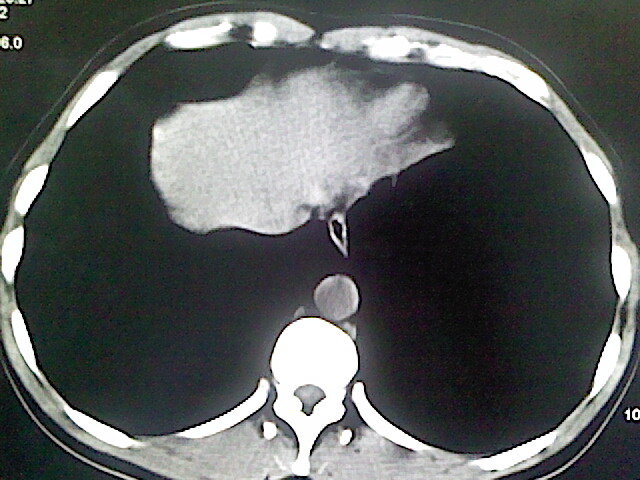

以下是引用卜一在2009-3-14 9:49:00的发言:[br]胆囊萎缩,胆囊壁不规则增厚,内部结构模糊,增强明显强化。另:肝左叶外侧段肝囊肿。支持:慢性胆囊炎!高度可疑:胆囊癌!

以下是引用余辉在2009-3-14 8:48:00的发言:[br]1)慢性胆囊炎。2)肝左叶外侧段肝囊肿。3)脂肪肝。[br]支持,胆囊萎缩,密度增高,不知b超具体有何提示,钙胆汁?结石?

以下是引用jiangjing在2009-3-14 10:18:00的发言:[br]1)慢性胆囊炎。2)肝左叶外侧段肝囊肿。3)脂肪肝。4.】建议行肝功能检查